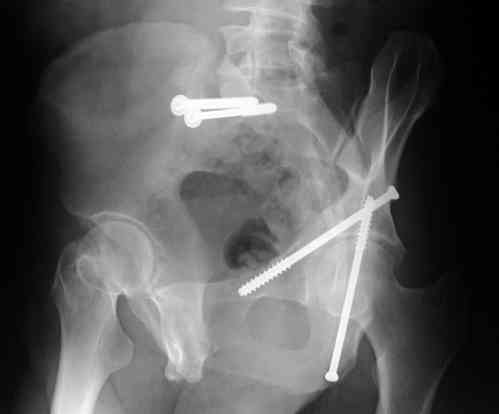

Screw Fixation

-AC Screw

-PC Screw

For Alex... here are some cannulated and 7mm screws for you... notice the fracture malreduction as indicated by the head subluxation on both views...this was a percutaneous technique without open reduction... I don¹t like it but there it is... the fixation technique is not at fault, because there was no open reduction of the fracture... but let¹s not get in to all that.